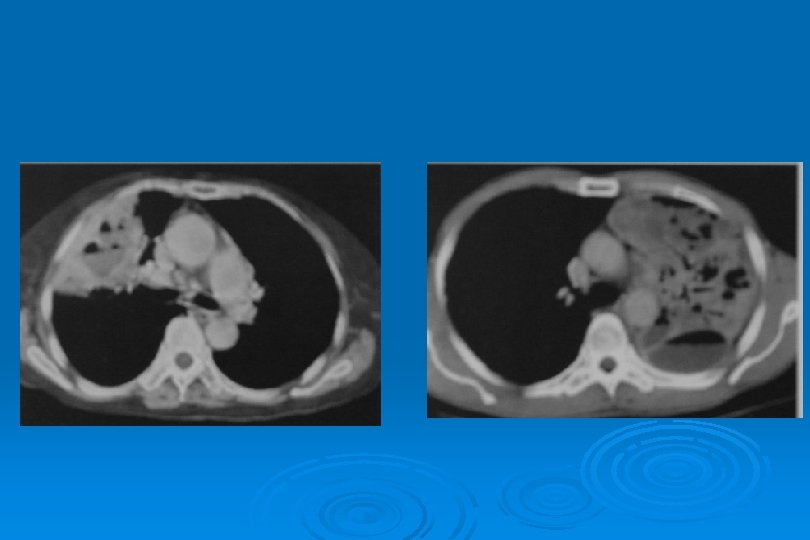

SİTOMEGALOVİRÜS • Birden fazla odakda, iki taraflı buzlu cam yoğunluğu ve konsolidasyon alanları • Milimetrik nodüller